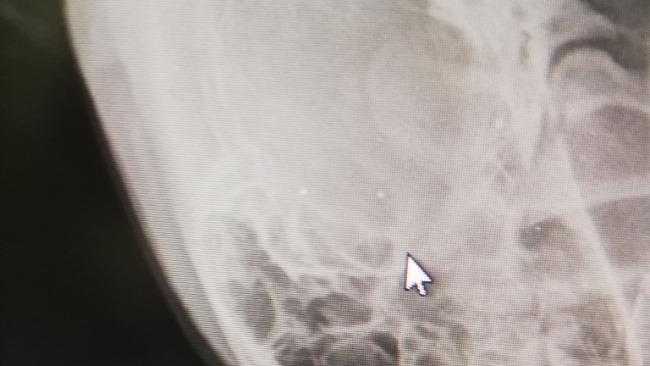

Ktoś do niego strzelał z broni długiej. W głowie kilka kyl - widać na rtg. Jeden pocisk trafił w oko ... oko wyleciało z oczodołu :(

W udzie była kula i mnóstwo odłamków kostnych. Pocisk wyleciał na zewnątrz, przebił skórę, ale pogruchotał tak kość, że rozprysła się na milion kawałków.

Pomóżcie nam uzbierać fundusze na tego psa - rtg, porządek z okiem. Co z nogą ? Nie wiemy ... jedną z opcji jest amputacja, ale o tym nie chcemy myśleć :( Przetoka nigdy się nie zagoi bo nie pozwolą na to odłamki :(